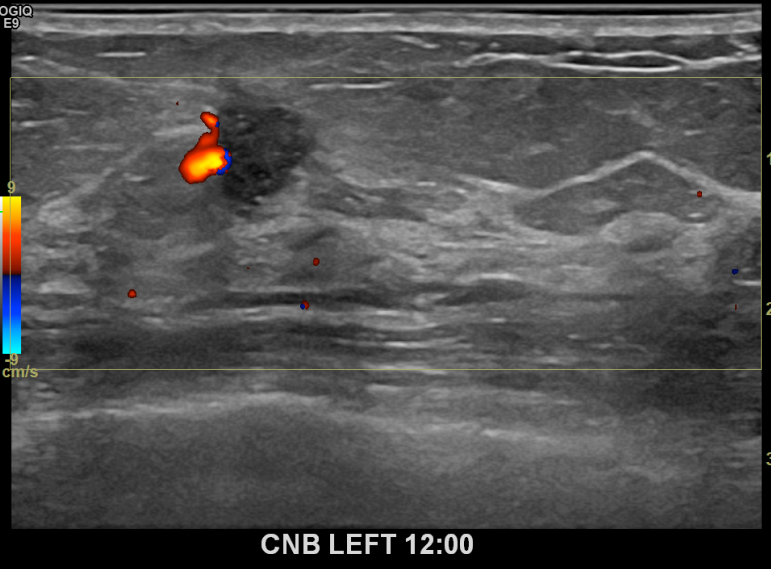

아산유외과개원후 724번째 유방암진단

상기환자 건진상 이상소견으로 조직검사권유받고 내원하신 70대 여성분으로 좌측유방멍울 조직검사시행후 유방암 진단되었습니다.